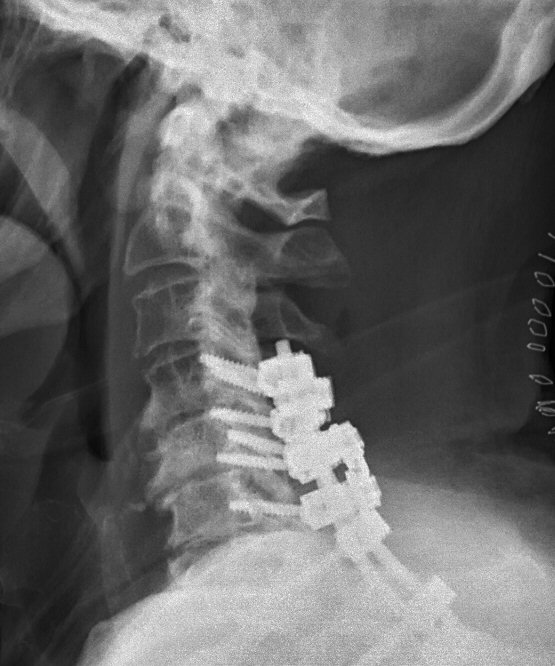

Distraktion mellan C6 och C7, opererades med bakre stag